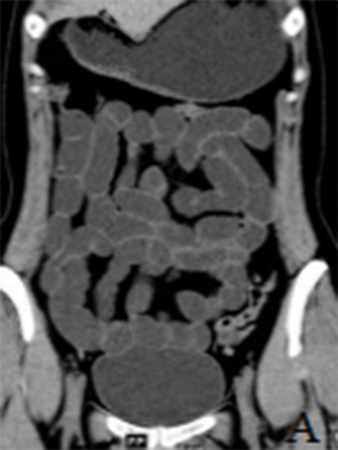

正常小肠影像

为了提高我院小肠疾病的CT诊断准确率,我科室先后外派人员到上海、广州等地进修学习,并于今年初开展此项检查,至今已开展了10余例,并取得了良好效果。病例展示如下图A-C。(玉溪市人民医院CT室 魏忠荣 高丽)